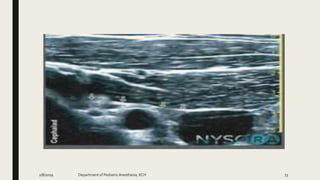

TAP-Types

2/8/2019 Department of PediatricAnesthesia, KCH 92